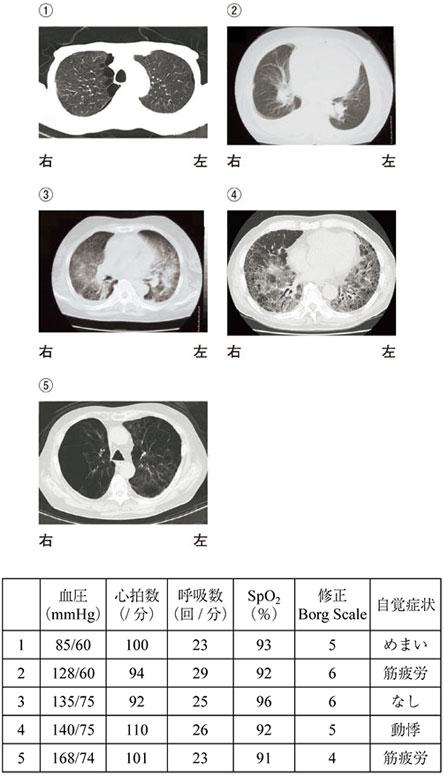

問題17の連続問題全身持久力トレーニングを行う場合、トレーニングを中止すべき状態はどれか。2つ選べ。トレーニング前の所見は、血圧120/65 mmHg、心拍数85/分、呼吸数19回/分、SpO296%、修正Borg Scale 3であった。